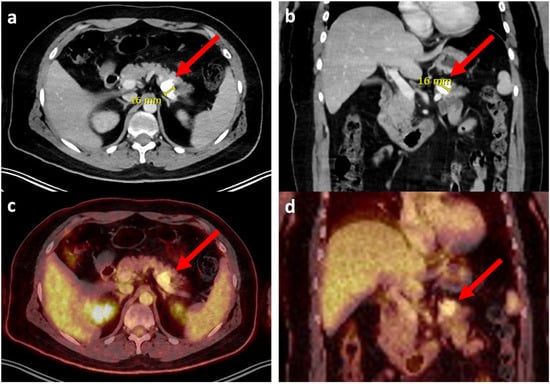

| 1 | 35 | m | osteoblastic (G3) | distal femur | CTx, OP, CTx (EURAMOS) | 129 | none | pancreas | single | 16 | yes | left pancreatectomy with splenectomy and gastric wedge resection | none | AWD | 8 |